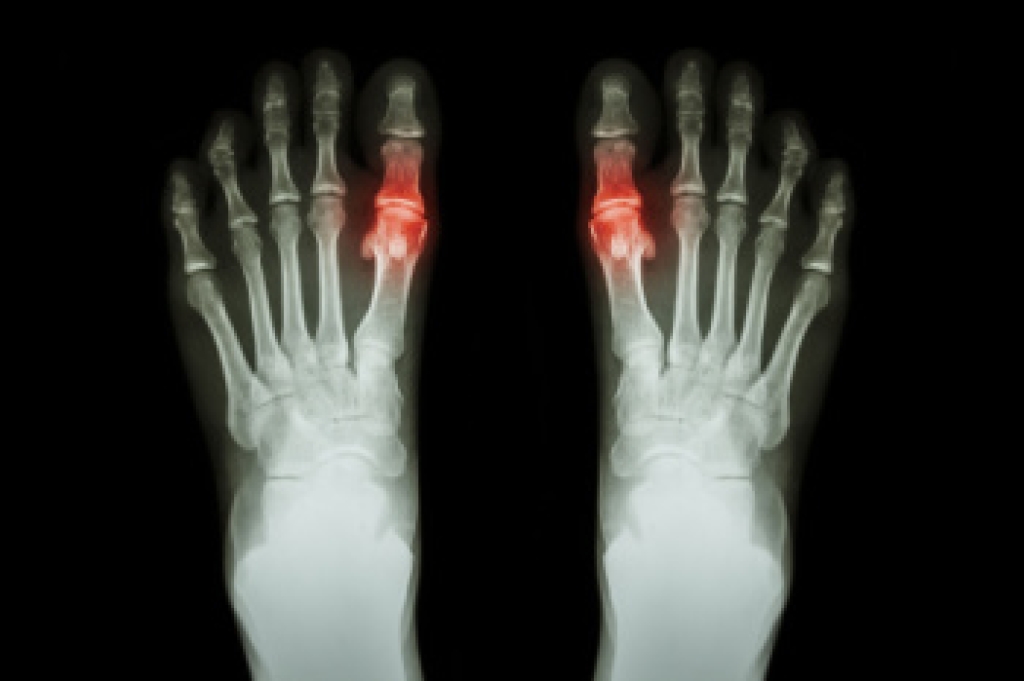

Gout is a type of arthritis caused by a buildup of uric acid in the bloodstream. It often develops in the foot, especially the big toe area, although it can manifest in other parts of the body as well. Gout can make walking and standing very painful and is especially common in diabetics and the obese.

Gout can easily be identified by redness and inflammation of the big toe and the surrounding areas of the foot. Other symptoms include extreme fatigue, joint pain, and running high fevers. Sometimes corticosteroid drugs can be prescribed to treat gout, but the best way to combat this disease is to get more exercise and eat a better diet.